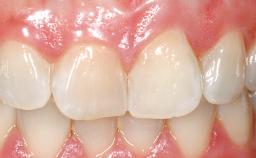

Immediate Placement of an Implant in a Maxillary Left Central Incisor Site

A 33-year-old female patient presented with an upper left central incisor that required extraction after a failed endodontic therapy. The tooth had been traumatized when the patient was a teenager and had undergone several endodontic treatments, including two apicectomy procedures. The patient was in good health and did not smoke. Clinical examination showed that the patient had a high lip line. In full smile, the gingival margins of the upper teeth were visible to the first molars. The gingival margins of central incisors 11 and 21 were only just showing. Examination of tooth 21 confirmed that the tooth was mobile and had hypererupted by 1 mm.

| Prosthesis Type | FDP |

| Lip Line | No exposure of papillae | Exposure of papillae | Full exposure of mucosa margin |

| Soft Tissue Contour and Volume | Slightly compromised |